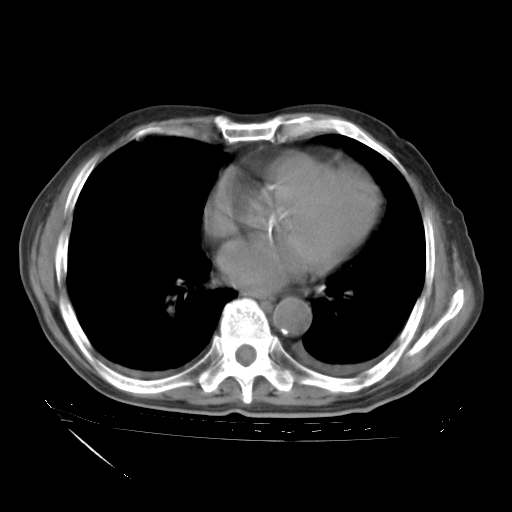

经过24天治疗,岳父的病情基本稳定。生活基本可以自理,可以下床活动。呼吸困难早已消失。体温基本正常。

主要治疗甲强龙80mg×14天,60mg×10天;同时抗结核(异烟肼+利福平+乙胺丁醇)。环磷酰胺0.1 tid 10天。

特别感谢胡教授、高管、桃子版主给出关键的治疗建议。桃版把所有肺部影像和全部临床资料请所在医院呼吸科、感染病科、结核科、临床免疫科专家会诊。临床免疫科专家制定了完整的治疗方案。